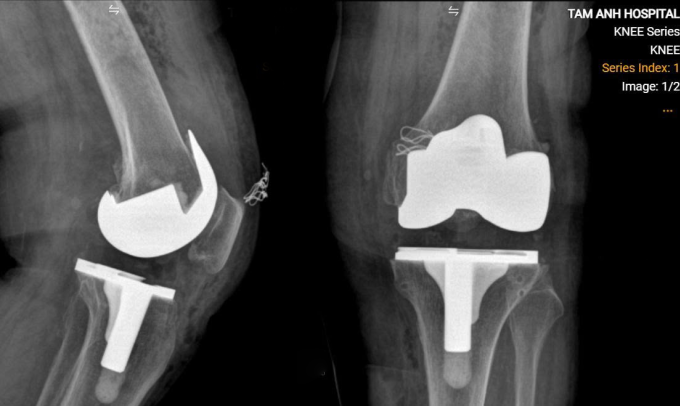

Bác sĩ chụp cắt lớp vi tính CT, tái tạo khớp gối lên môi trường 3D, giúp đo đạc chính xác các thông số để chọn loại khớp phù hợp, xác định vị trí và hướng đặt khớp, cân bằng sức căng dây chằng cho bà. Khi mổ, bà Tịch được gây tê tủy sống, kết hợp thuốc an thần nhẹ để ngủ thoải mái, tránh biến chứng của gây mê toàn thân. Bác sĩ Nghĩa rạch bộc lộ khớp gối, cắt xương và đặt khớp nhân tạo cho người bệnh, hơn một tiếng ca mổ hoàn thành.